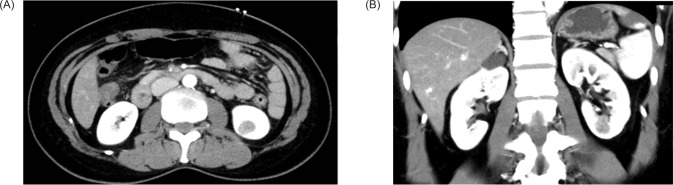

Mucinous tubular and spindle cell carcinoma (MTSCC) is a rare type of renal cell carcinoma (RCC) recognized as an independent entity in the latest WHO (World Health Organization) classification. We here report a case of a 51-year-old female patient with MTSCC, who presented with abdominal pain and left lower pole kidney lesion on the computed tomography scan. A robotic-assisted laparoscopic partial nephrectomy was performed. The diagnosis was confirmed on histopathological examination. MTSCC is rare and generally indolent. Either partial or radical nephrectomy is usually curative. The prognosis is usually favorable. However, occasionally, MTSCC could demonstrate aggressive features requiring systemic therapy. There are also several mimickers of MTSCC, which carry different prognostic and treatment profiles. Histological, immunohistochemical, and molecular genetic profile are useful in diagnosing the disease.